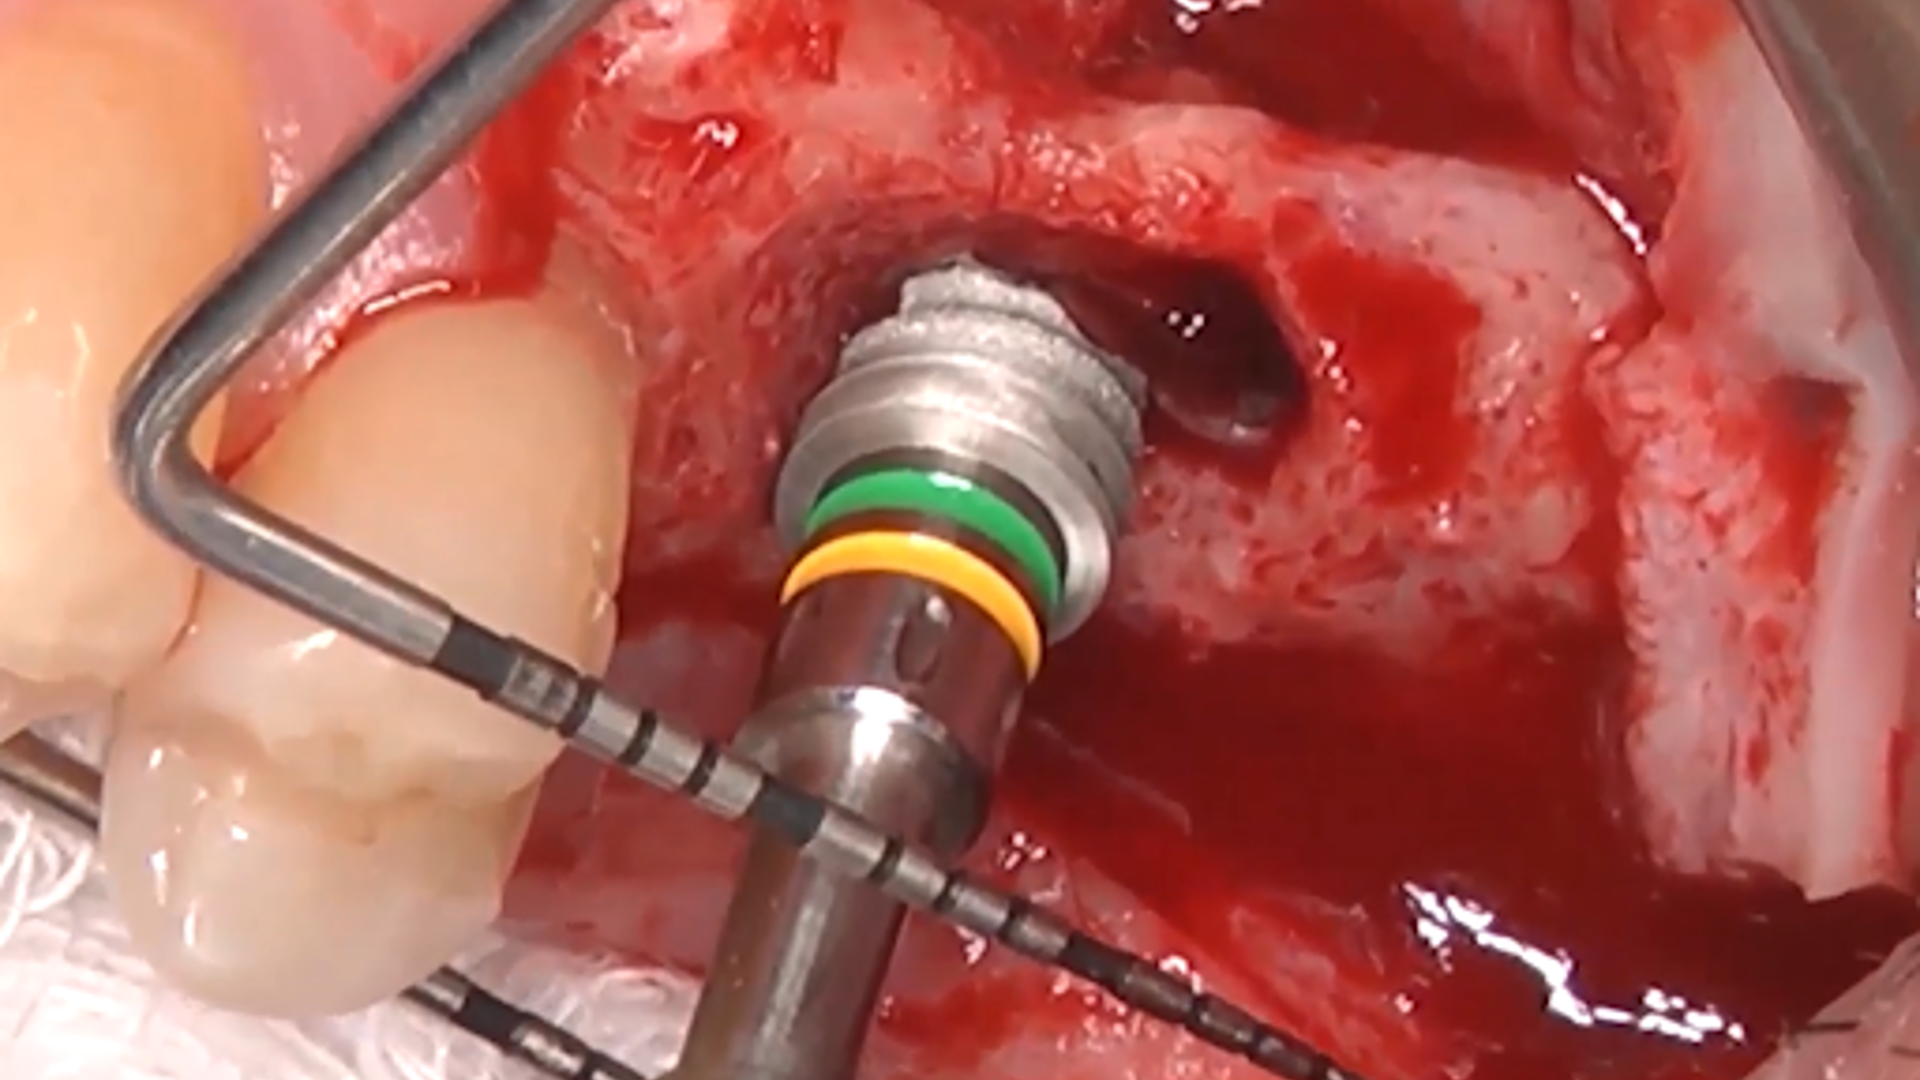

Evolution of sinus lift procedures: Piezo Surgery and Osseodensification

Osseodensification technique

Crestal Approach: the decision tree algorithm